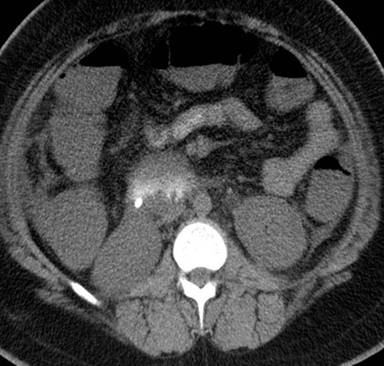

A 12-year-old previously healthy obese female presented with a 1-day history of progressive irritability and drowsiness. Her mother reported a 3-week history of polyuria, polydipsia and involuntary weight loss of 4.5 kg. She also complained of epigastric pain on the day of admission. On examination, she had tachypnea (with Kussmaul’s breathing), tachycardia and hypotension. She was drowsy and had moderate dehydration on assessment (6-9% fluid deficit). Investigations revealed hyperglycemia (511 mg/dL, reference range 74-106 mg/dL), acidosis (pH: 7.07, reference range 7.35-7.45; HCO: 3.5 mmol/L, reference range 21.0-32.0 mmol/L) and positive ketones and glucose in urine. She was started on fluid resuscitation and insulin therapy. Initial complete blood count showed a hemoglobin (15.7 g/dL, reference range 12-16 g/dL), leukocytosis (17,500 µL-1, reference range 4,500-13,500 µL-1), and a platelet count of 238,000 µL-1 (reference range 142,000-405,000 µL-1). Her ketoacidosis resolved within 24 hours and she was switched to subcutaneous insulin. Serum amylase and lipase were significantly elevated. Computed tomography (CT) scan of the abdomen demonstrated diffuse enlargement and hypoattenuation of pancreas with stranding of the peripancreatic fat and peripancreatic fluid collection, suggestive of pancreatitis (Figure 1). She continued to remain drowsy and was intermittently arousable to pain and verbal stimuli. A CT scan of the brain to rule out cerebral edema was negative. In spite of correction of dehydration, her blood urea nitrogen and creatinine were rising and she developed oliguria. Repeat complete blood count showed anemia (hemoglobin 10.6 g/dL), thrombocytopenia, and slight evidence of hemolysis (<5% schistocytes, reference range 0-5%). Her amylase and lipase were improving but LDH was slightly increased. Prothrombin time, plasma thromboplastin time, and fibrinogen were normal, while D-dimer was slightly elevated. In view of altered mental status, renal failure and thrombocytopenia, diagnosis of thrombocytopenia associated with multiple organ failure was considered. ADAMTS 13 (A Disintegrin And Metalloprotease with ThromboSpondin motifs; formerly known as von Willebrand factor cleaving-protease) activity was 52% (reference range: 70-150%). She was started on plasma exchange. She responded with 3 days of plasmapheresis with a dramatic improvement in her sensorium, renal function tests and platelet count. Table 1 shows the laboratory parameters of the patient at admission, before and after plasmapheresis.

Figure 1. CT abdomen showing diffuse enlargement and hypoattenuation of pancreas with stranding of the peripancreatic fat and peripancreatic fluid collection, suggestive of pancreatitis. |